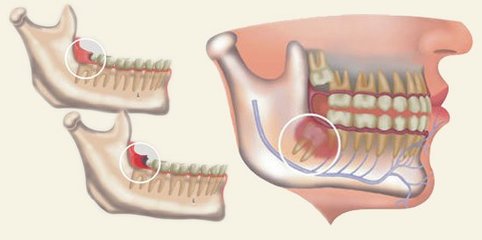

智齒發炎,也稱為(wei) 智齒冠周炎,主要是因為(wei) 智齒不能正常萌出,或者萌出一半位置不正對鄰牙造成擁擠,強力擠占牙齒位置造成,經常會(hui) 帶來劇烈的牙痛,而且還有牙齦紅腫的情況,甚至是影響吃飯和睡覺,非常難受。...

智齒發炎,也稱為(wei) 智齒冠周炎,主要是因為(wei) 智齒不能正常萌出,或者萌出一半位置不正對鄰牙造成擁擠,強力擠占牙齒位置造成,經常會(hui) 帶來劇烈的牙痛,而且還有牙齦紅腫的情況,甚至是影響吃飯和睡覺,難受。那麽(me) 一般要怎麽(me) 治療呢?

為(wei) 什麽(me) 要拔除智齒,因為(wei) 智齒是多出來的牙齒,其實是沒有牙齒功能的,而且拔除後是不需要鑲牙修複的,如果位置不正,留在口腔內(nei) ,不僅(jin) 會(hui) 反複出現炎症的情況 ,而且還會(hui) 引起牙齒擁擠的情況。所以建議及時拔除比較好,早點拔除,就可以避免長期的危害。